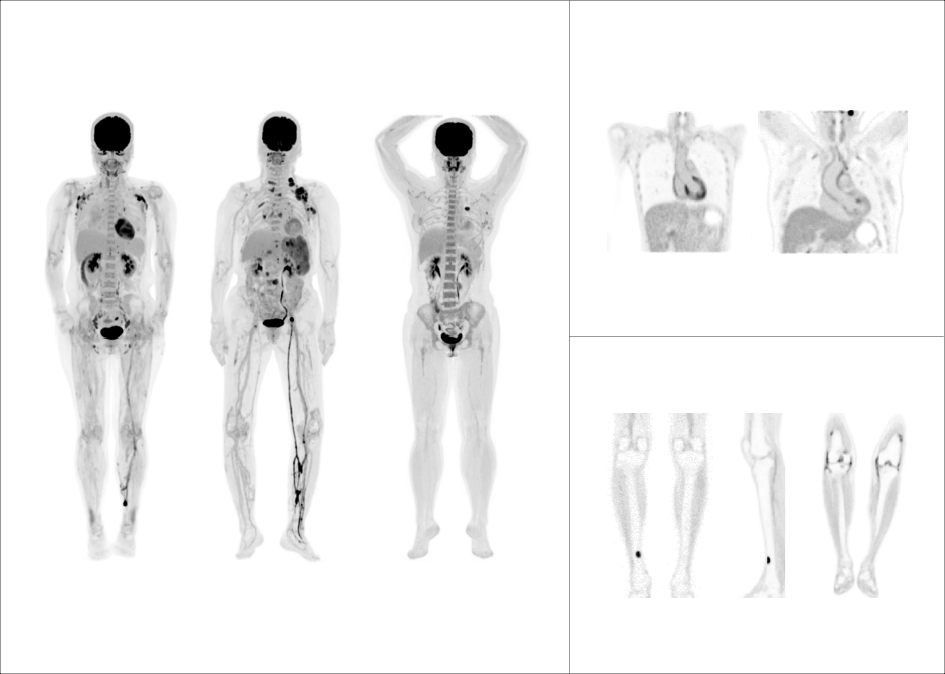

支持68Ga、 90Y、18F、82Rb、15O等不同半衰期、不同核素药物高清显像

临床应用

微小淋巴结高清显像

鼻咽癌头颈部单床位大范围扫描

肺癌胸腹部单床位大范围延迟扫描

大体重患者主动脉血管结构清晰显示

68Ga-DOTA-NOC PET/CT 高清显像